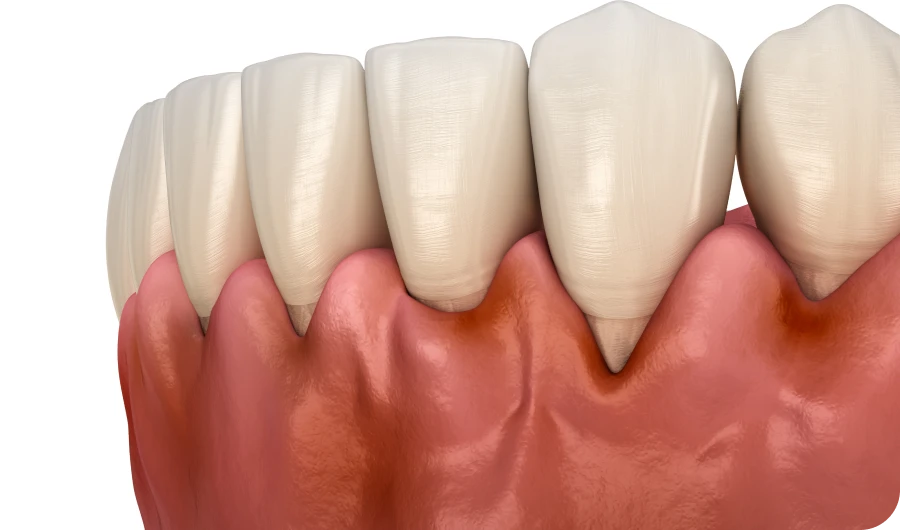

Découvrez les principales affections bucco-dentaires : parodontite, récession gingivale, dents de sagesse, kystes et abcès dentaires. À travers des contenus clairs et illustrés, nous vous expliquons leurs causes, symptômes et options de traitement. Mieux comprendre ces pathologies, c’est mieux prévenir et soigner.